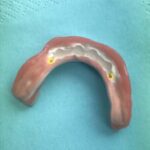

Patientenfall, zahnloser Unterkiefer. Komplett metallfreie Lösung. Der Zirkonium-Steg auf 4 Implantaten garantiert einen absolut festen Sitz, Sicherheit und Kaukomfort.

4 Implantate im Kinnbereich

Ein Zirkoniumsteg zur Befestigung des Zahnersatzes

Steg auf dem Modell

Unterkiefertotalprothese auf PEEK-Gerüst

Prothese von unten